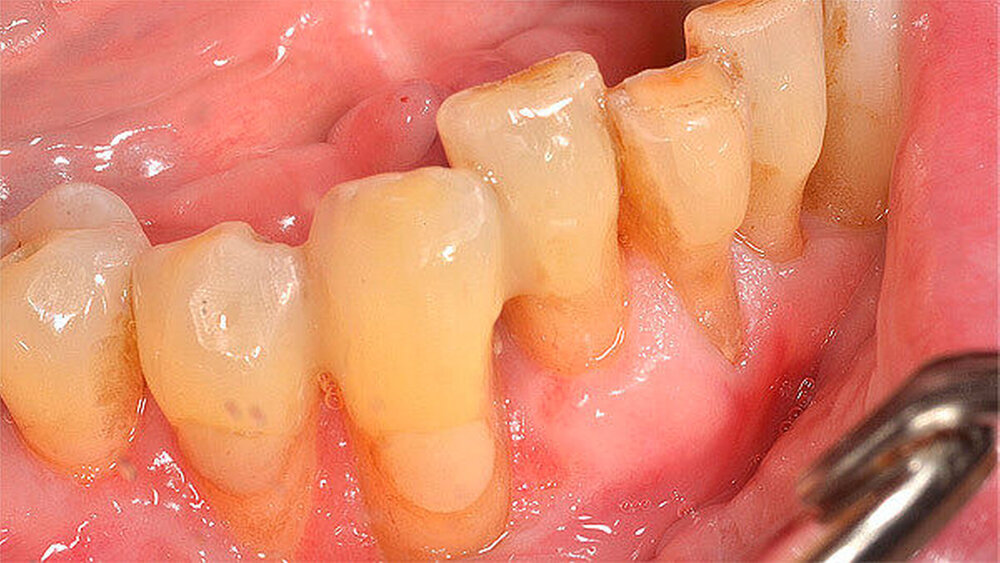

Nach 48 Stunden i.v.-Antibiose und intensiver Hygienisierung (Abbildung 3) erfolgte die Abtragung der Gingivanekrose unter laufender Dabigatran-Medikation. Die sich von Zahn 32 bis 35 vestibulär und interdental erstreckende Nekrose wurde schonend entfernt (Abbildung 4). Eine Mitbeteiligung des Alveolarknochens war nicht erkennbar. Im Anschluss erfolgte eine chemische Dekontamination der Wunde mit Betaisodona-Lösung sowie der primäre Wundverschluss mittels modifiziertem koronalen Verschiebelappen (Nahtmaterial: Resolon 4.0, Resorba Medical GmbH). Die Zähne 32 bis 34 wurden aufgrund ihrer geringgradigen Lockerung belassen und mittels Säure-Ätz-Technik primär durch Schienung stabilisiert. Abschließend erfolgte die Abdeckung des OP-Situs mit einer Verbandsplatte, in welche im vestibulären Bereich eine Aussparung eingearbeitet wurde (Abbildung 5).